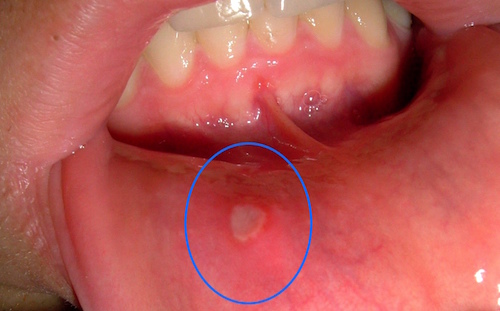

舌、唇にできた白い口内炎とは

舌や唇に出来る白い口内炎ですが、

アフタ性口内炎と呼びます。

どうして白いかというと、

これはタンパク質によるもので、

傷口で血液が固まる際に、

タンパク質が偽膜を作るためです。

このアフタ性口内炎は、

2つの口内炎がくっついて大きな口内炎になるということもあり、

その場合は非常にたちが悪いです。